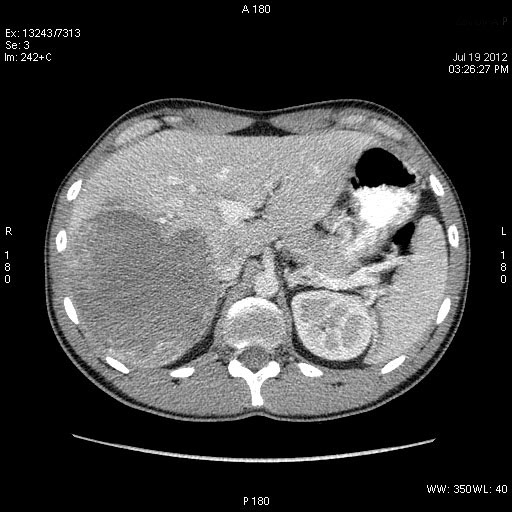

Молодой человек, наркоман, поступил в хирургическое отделение с подозрением на абсцесс печени.

Жалобы на высокую температуру, слабость.

КТ через день

Что-то не укладывается именно ультразвуковая картирка в абсцесс печени.

После КТ хирурги заказали дренирование "абсцесса".

Выполнена диагностическая пункция из 4х участков, получена только кровь.

на узи на абсцесс не похоже, образование солидное ----гепатома?

Гигантская капилярная гемангиома печени.